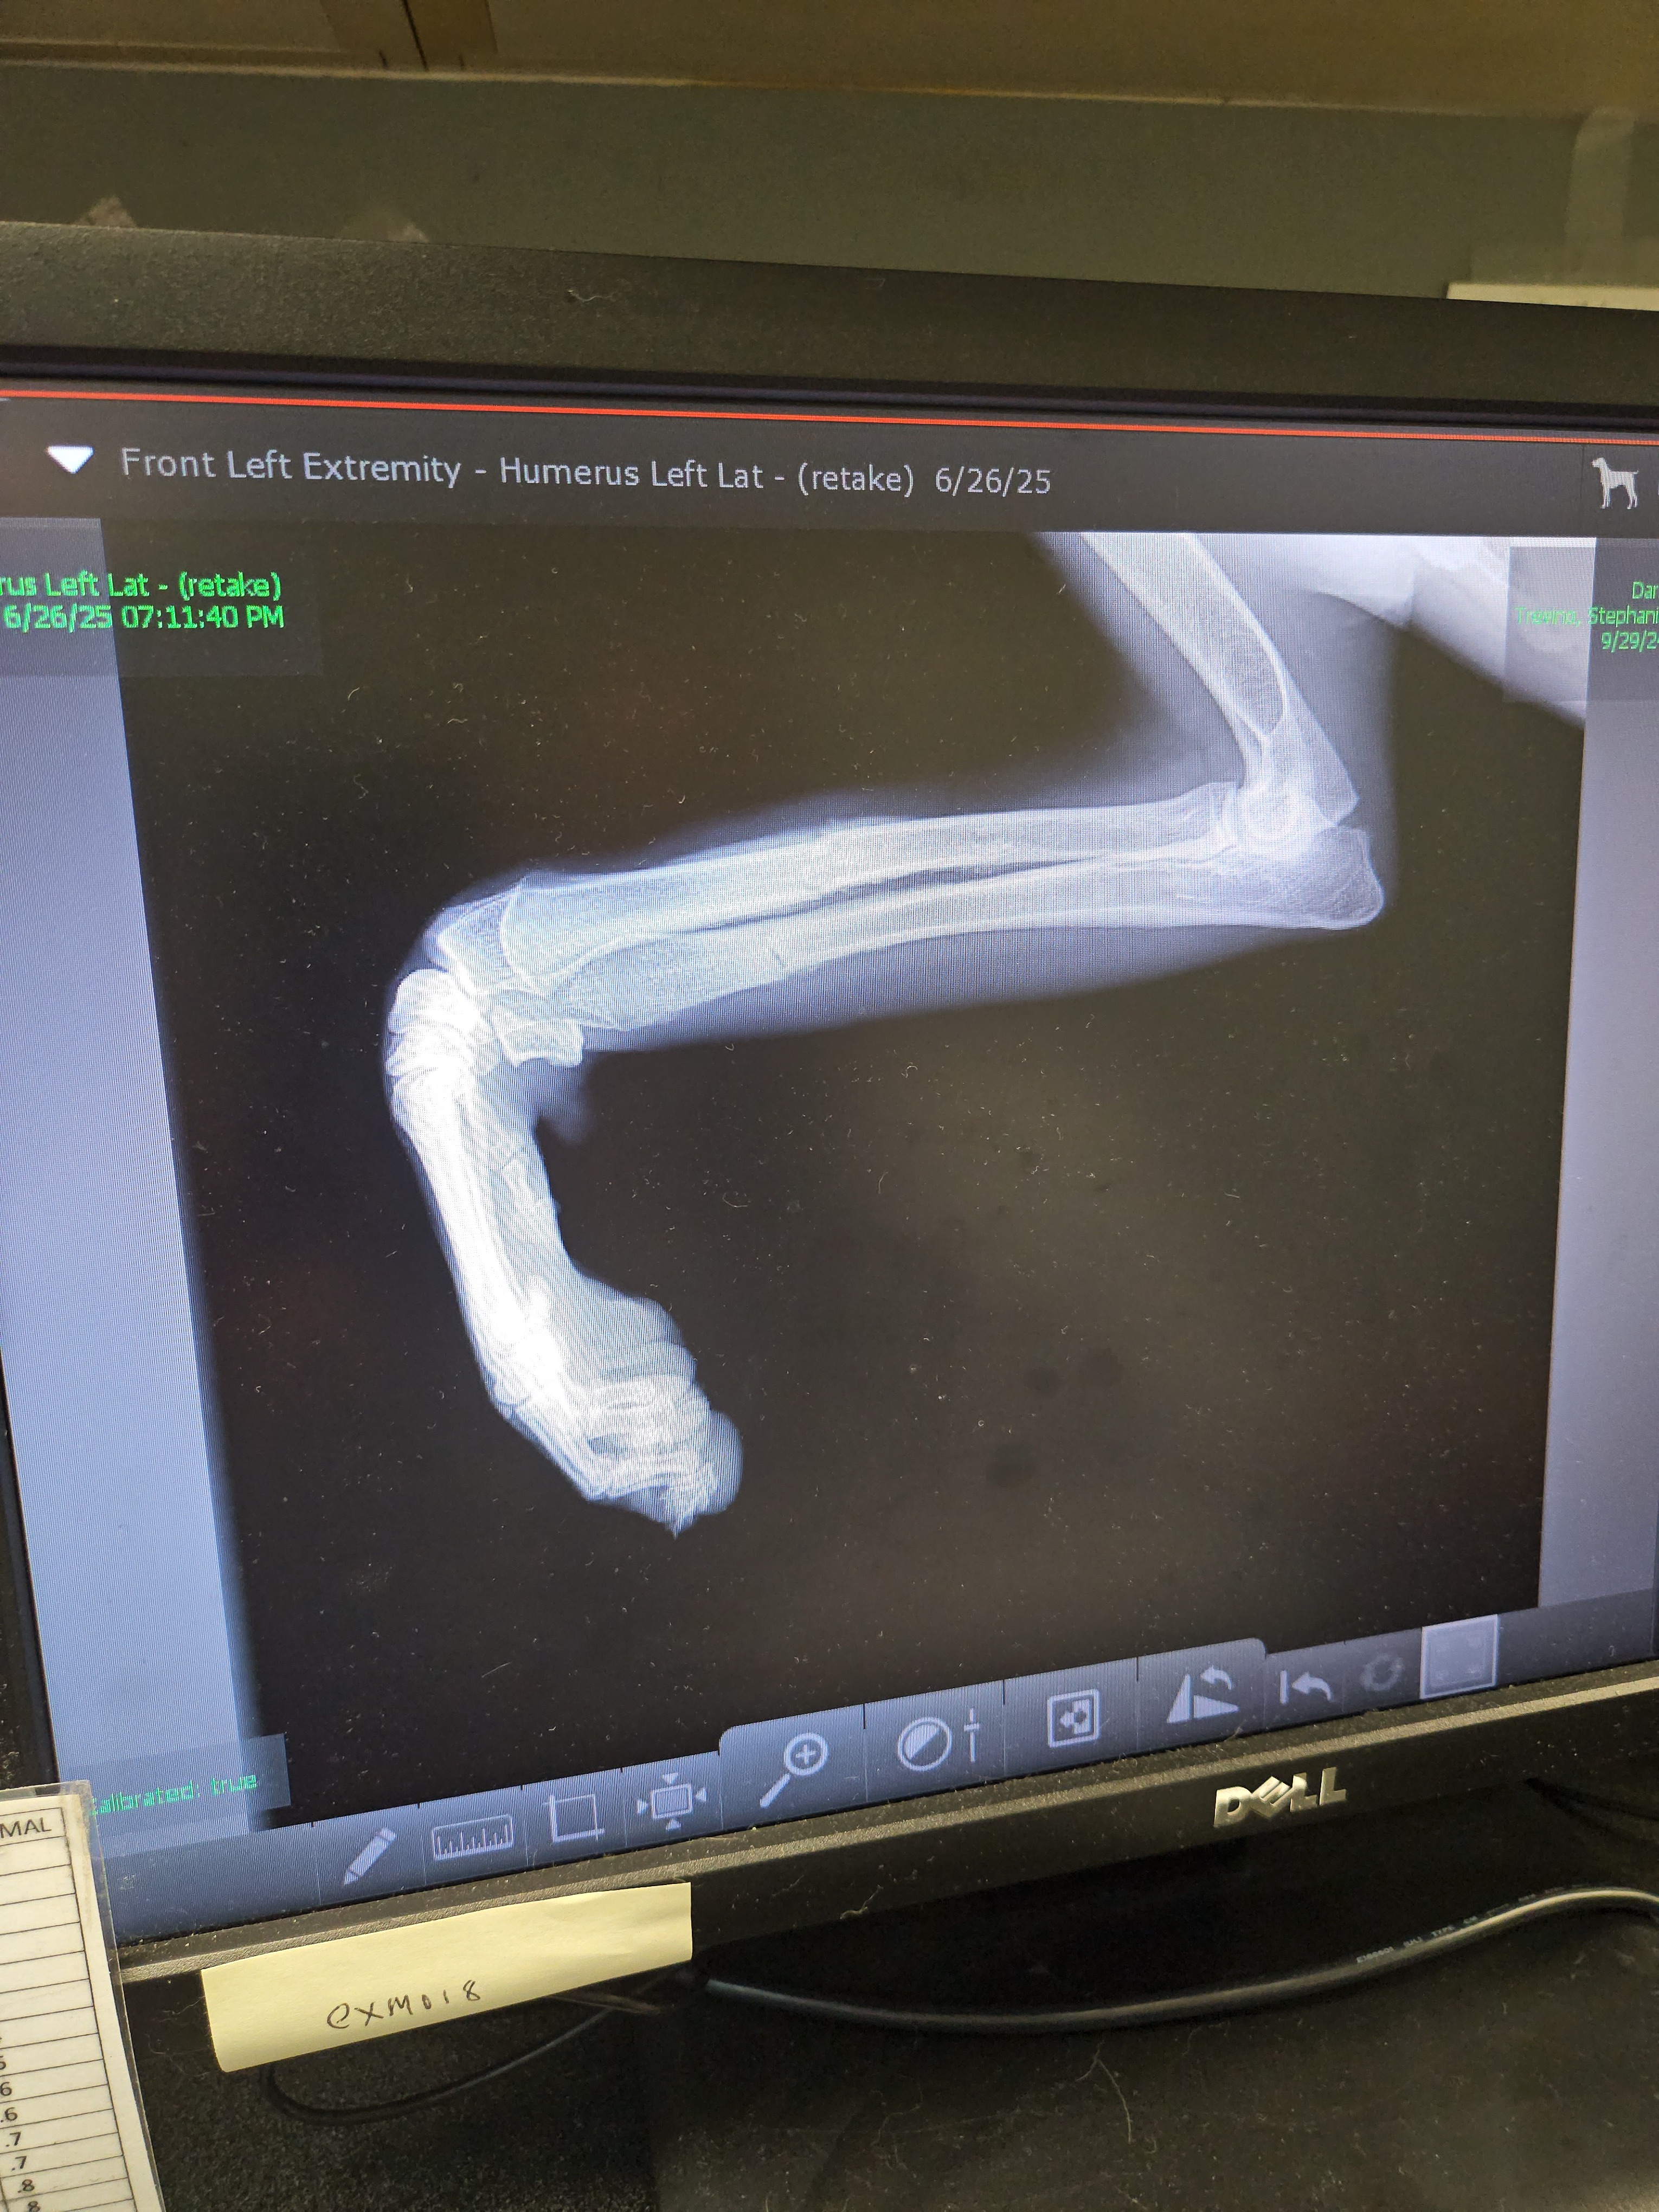

Darla is our 8-month-old Saint Bernard who escaped out of our fenced yard. She had to be trapped by a trapper who generously donated his time because she was on the run for so long. Sometime during the 14 days she was on the run, she was hit by a car, fracturing her leg and shoulder. The leg has started to heal, and the only option is going to be possible orthopedic surgery. We are fortunate enough to have some money put aside and our care credit but are still coming up short.